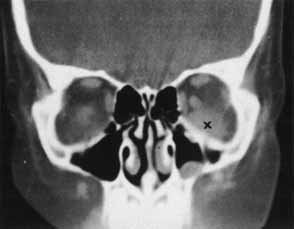

Fig. 3 CT scan of inferior orbital hematoma (X) involving the inferior rectus muscle and causing severe upgaze and moderate downgaze limitation.